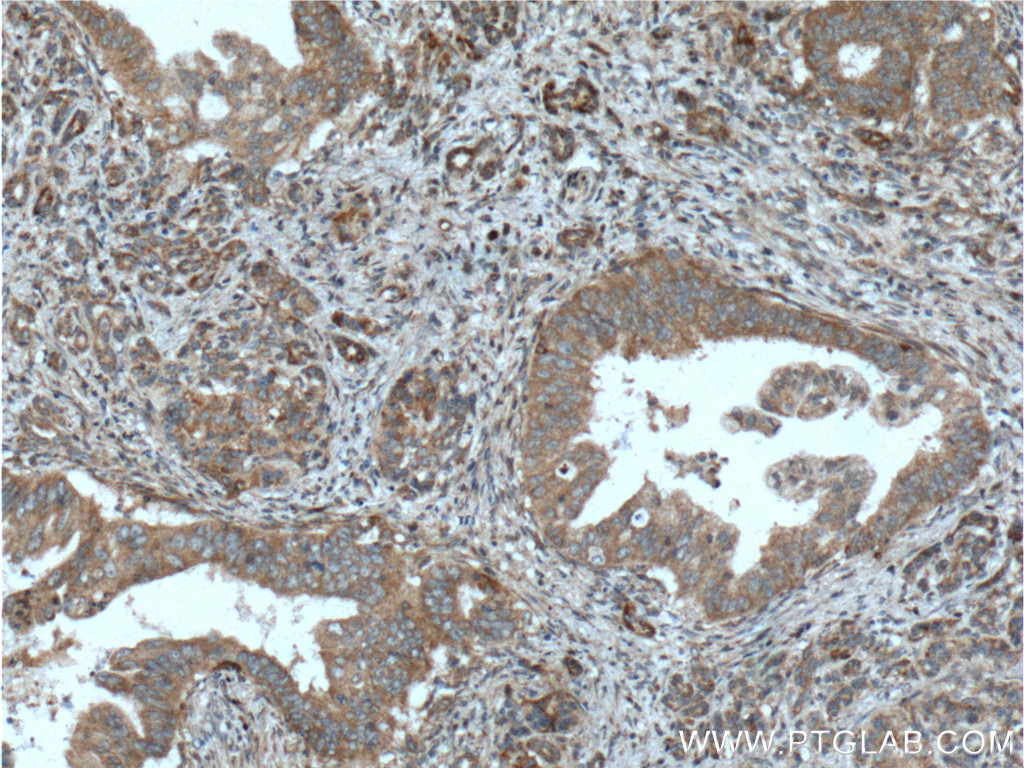

| Positive IHC detected in | human pancreas cancer tissue Note: suggested antigen retrieval with TE buffer pH 9.0; (*) Alternatively, antigen retrieval may be performed with citrate buffer pH 6.0 |

| Immunohistochemistry (IHC) | IHC : 1:50-1:500 |